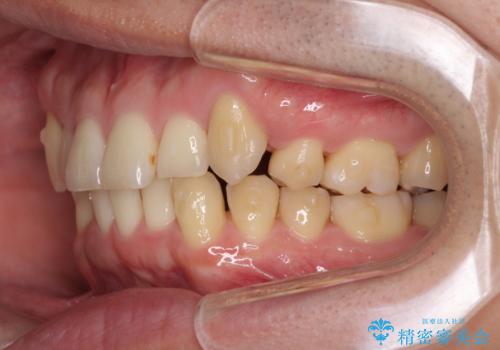

- 上顎の八重歯と前歯のデコボコを気にして来院された患者様です。

八重歯の移動量が多く、インビザライン単体での治療は困難と判断し、補助装置により八重歯移動後にインビザラインを用いることとしました。

上顎のみの抜歯矯正をインビザラインで行う場合、奥歯の前方移動がインビザラインでは苦手のため、奥歯の咬み合わせが不十分となることがあります。

今回の治療では終了時に奥歯は接触しているものの、接触の程度は物足りないものがある状態でした。今後保定期間に少しずつ奥歯の咬合を改善させていくことになります。